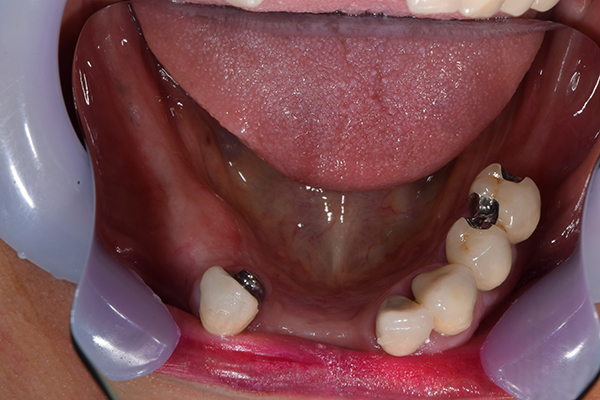

ケース3(インプラントを用いた部分入れ歯)

右上と左下の歯がない方です。 上の入れ歯の安定が悪く、作り直したいとのことでいらっしゃいました。 今お使いの上の入れ歯を見てみると、口蓋部分が抜けており、安定性に欠ける構造になっていました。この入れ歯はノンメタルクラスプデンチャーといって、金属のバネを使用しない 入れ歯になります。これは見た目は良いのですが、歯への負担が大きいことと、入れ歯自体がやわらかいため、噛むには不便なことがあります。

入れ歯は極力薄くするために金属を使用しました。しっかり噛める様にするため、ノンメタルクラスプデンチャーにはしませんでした。

上の入れ歯(表)

上の入れ歯(裏)

下の入れ歯

入れ歯を入れた状態のお口の中の写真です。バネも極力目立たないように作成しています。

年齢 70代・女性

主訴 上の入れ歯の安定が悪く、作り直したい

治療期間 5ヶ月

治療費 .診査診断:55,000円

.インプラント埋入:165,000円

.アバットメント:33,000円

.義歯:330,000円

治療方針 右片側のみ奥歯がない方です。

この様な場合入れ歯は反対側に維持を求めるため、大きな入れ歯になりがちです。

そのため違和感が強いことがおおいです。

また、片側だけないですので、安定もむずかしくなります。

そこで、安定をよくするために、右の奥歯の位置にインプラントをいれて、義歯が揺れない様にすることにしました。

治療内容 レントゲンをみて最低限の長さのインプラントを右上の奥歯の位置に埋入しました。インプラントと骨の結合(オッセオインテグレーション)と歯肉の治癒を待ち、アバットメントをいれて型取りをして、入れ歯を作成しました。極力薄くするために、金属をもちいた入れ歯にしました。

特記事項 インプラントは必ず成功するというものではありません。 また治癒も人それぞれで、長くかかることもあります。 入れ歯を入れ終わったあとも、アバットメントが緩んできたり、入れ歯が歯ぐきにあたって痛いところもでてきますので、調整は必要になります。